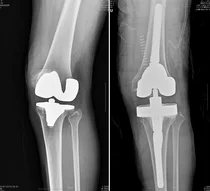

연세사랑병원, ‘PNK 인공관절’ 식약처 허가 획득

연세사랑병원은 후방십자인대를 보존하는 한국형 인공관절 CR타입을 개발, 식품의약품안전처 허가를 받았다고 1일 밝혔다. 현재는 FDA의 승인 절차를 밟고 있어 코렌텍에 이은 국산 인공관절의 성공적인 해외 진출에 대한 기대가 모인다. 앞서 연세사랑병원 인공관절 ...

한국형 인공관절 수술 후, 간호간병 통합서비스로 환자 부담 줄일 수 있어

퇴행성관절염은 뼈와 뼈 사이에서 하중 부담과 완충 역할을 하는 연골이 노화나 과도한 사용으로 인해 닳아 염증과 통증이 발생하는 질환이다. 고령화 사회에서 흔히 발생하는 질환 중 하나로 초기 치료가 중요하다. 하지만 초기에는 경미한 무릎 통증으로 휴식을 취하면 증상이 개...

인공관절 수술 후 회복 집중 위해선?

퇴행성관절염은 뼈와 뼈 사이에서 하중 부담과 완충 역할을 하는 연골이 노화나 과도한 사용으로 인해 닳아 염증과 통증이 발생하는 질환이다. 고령화 사회에서 흔히 발생하는 질환 중 하나로 초기 치료가 중요하지만 초기에는 경미한 무릎 통증으로 휴식을 취하면 증상이 개선돼 알...

쪼그려 앉는 자세가 통증 유발...‘한국형 인공관절’ 치료

농사를 업으로 삼는 사람부터 취미로 텃밭을 가꾸는 사람까지 봄은 신선한 작물을 직접 키우는 이들에게 중요한 시기다. 다만, 밭일이나 나물을 채취하는 작업은 오랫동안 같은 자세로 무릎을 쪼그려 앉거나 허리를 구부려서 근골격계에 무리를 주는데 이에 따른 대표적인 질환이 &...

‘만성염증’ 퇴행성관절염, 말기에는 ‘한국형 인공관절’로 개선

염증은 특정 부위의 손상이나 감염이 진행됐을 경우 이에 대한 손상을 줄이고 정상화하려는 우리 몸의 방어 반응이다. 면역세포를 이용해 해당 조직의 손상을 최소화하고 감염체를 제거 또는 막는 역할을 한다. 문제는 특정 부위에 염증이 지속되면서 발생하는 만성염증이다. 만성염...

인공관절 재수술, 경험 많은 의료진이 결과 좌우

82세 A씨는 퇴행성관절염 말기 무릎 통증으로 16년 전 인공관절 치환술을 받았다. 하지만 빙판길에 넘어지면서 3년 전부터 다시금 통증이 시작됐고, 고심 끝에 병원을 찾은 그는 ‘인공관절 재치환술’을 해야 한다는 진단을 받았다. 그러나 A씨를 반기...

한국형 인공관절, 움직임·이물감 없는 사용감으로 환자 치료 적용

무릎 연골은 일상생활 중 다양한 역할을 담당하는 신체 기관으로 반복적인 노출에 따라 손상되기 쉽다. 연골이 마모되기 시작하면 가벼운 아픔을 시작으로 강한 통증을 호소하기 쉬운데 초, 중기 증상에 따라 적용되는 치료는 매우 상이하다. 연골의 양이 적게 훼손된 상황이라면 ...